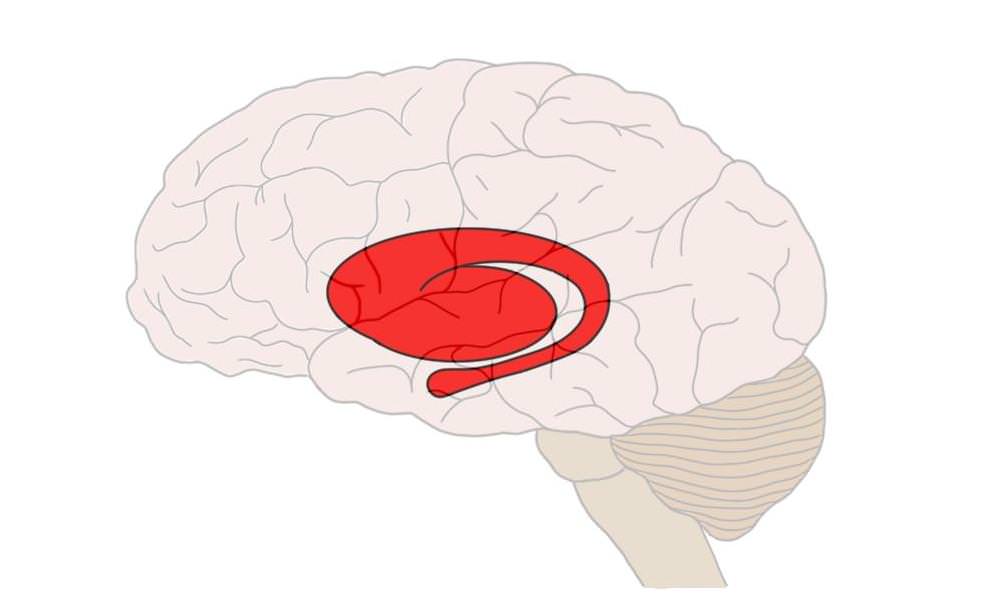

Le striatum est un loup pour l’homme

Saviez-vous que notre cerveau, conformément à la théorie de l’oignon développée par Shrek en 2001 (ouais ouais, 20 ans l’an prochain), s’était développé couche par couche ? C’est donc assez logiquement que l’une de ses parties les plus anciennes se terre dans ses obscurs tréfonds : le striatum… Ce sympathique Alien rouge, niché au creux de notre encéphale, est en charge depuis des lustres chez nombre d’organismes (lamproie, singe, humain, Narfi) de piloter le « circuit de la récompense« . Ce chaînage biologique et chimique associe à certains comportements ciblés une certaine quantité de dopamine, substance suscitant chez l’animal un plaisir intense et… addictif. Comme mes articles, oui, tu peux dire ça. Pour reproduire et maintenir cette sensation de bien-être, le stimulus doit sans cesse être réitéré, plus intensément : et la dose, augmentée. Autrement dit, notre fonctionnement primordial tend vers une surconsommation : et rien ne nous dispose naturellement, dans sa structure, à la modération.

De tous les points évoqués, le dernier présente l’avantage comparatif d’être réversible. Si l’accumulation boulimique d’informations et de stimuli résulte de l’activité du striatum, notre récent cortex, pour sa part, pilote les fonctions d’inhibition de notre cerveau. Il permet ainsi de ressentir un vif et long plaisir lors d’expériences plus contemplatives, lentes ou sereines, voire dans l’attente même de celles-ci. L’un des exemples cités par Bohler est celui du grain de raisin, promu par le psychiatre Christophe André (voir ci-dessous), particulièrement féru de méditation et de sobriété. Cette expérience sensorielle, notamment utilisée dans le traitement des pathologies de l’alimentation (boulimie par exemple), consiste à maximiser le temps de consommation d’un simple fruit sec. Les résultats en sont édifiants : sentiment de satiété, plaisir décuplé, découvertes sensorielles, durabilité des sensations éprouvées…